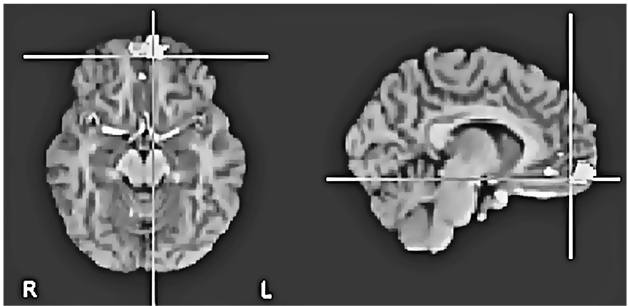

«Не уверен», как и предполагалось, активизировала переднюю поясную кору – своего рода нейронный сигнальный свет, вспыхивающий при внезапном появлении на горизонте чего-то нового и загадочного (рис. 8.1c (i) и (ii)).

Рис. 8.1c (i – вверху) и 8.1c (ii – внизу). Повышение активности во фронтальной части поясной извилины и в верхней лобной извилине при оценке утверждений, не поддающихся проверке («не уверен»). Рис. 8.1c (i) показывает разницу в активности по сравнению с картиной восприятия суждений, вызывающих доверие. Рис. 8.1c (ii) показывает разницу с картиной восприятия суждений, вызывающих недоверие (по материалам Харриса и др., 2008)